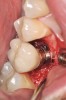

Fig 15. Implant abutment following cement removal.

Fig 14. Clear resin cement left on the implant abutment.

If all implant-supported crowns could be designed for screw retention, no discussion of excess cement would be necessary. However, screw retention is not always possible depending on the location of the access opening and because of the unesthetic appearance in anterior restorations or the mesial/distal angulation of the implant compromising the path of insertion (Figure 12). Residual cement left after crown cementation on implants can lead to peri-implant inflammation, peri-implantitis, and eventual loss of the implant (Figure 13 through Figure 15).25 The presence of lingering excess cement can encourage the development of bacterial colonization and peri-implantitis. Conversely, when too little cement is used, voids in the cement layer can occur and the prosthesis can become loose.26 The deeper the implant crown margin, the more difficult it is to remove excess cement.27

Radiopaque cements that contain zinc phosphate and zinc oxide (with and without eugenol) should be considered to help identify excess interproximal cement; however, this should be used secondarily to proper margin height and careful removal of cement during cementation. Resin cements lack the same opacity as zinc-containing cements and have been shown to be the most difficult to remove.28 Often in the process of removing this excess cement, the abutment surface becomes scratched and damaged, potentiating further plaque accumulation.29

Several modifications in abutment design and cementation have been suggested. Placing vent holes in the abutment during fabrication or leaving most of the screw-access chamber open for access has reduced the amount of cement that expresses out into the sulcus.26 It is also beneficial to extraorally express excess cement on an abutment replica prior to final crown seating to minimize complications. If retrievability is desired with cementable implant crowns, weaker cements (eg, zinc oxide eugenol) should be used first and progressively changed until the desired retention is achieved.